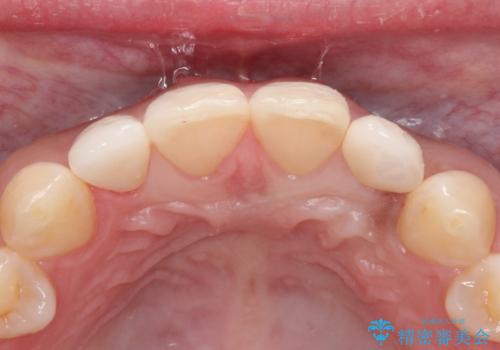

- 側切歯が小さいことを主訴に来院されました。

いくつかの治療の選択肢を説明し、オールセラミッククラウンで治療することとなりました。

長期的に安定した治療を求める場合はオールセラミッククラウンによる治療を提案します。